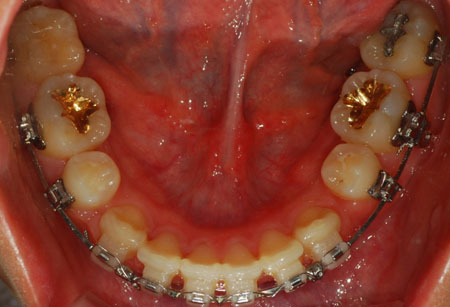

하악 사진

저기 동그라미 친 부분이 남은 발치 공간 입니다. 많이 줄어들엇죠?

친구가 저 틈을 보고 치아 뽑은지도 몰르더라구요ㅋㅋㅋ

노란 동그라미는 남은 발치 공간 입니다.

지금 파란 동그라미 보시면 그 공간이 거의 없습니다. 음하하하하하하핳